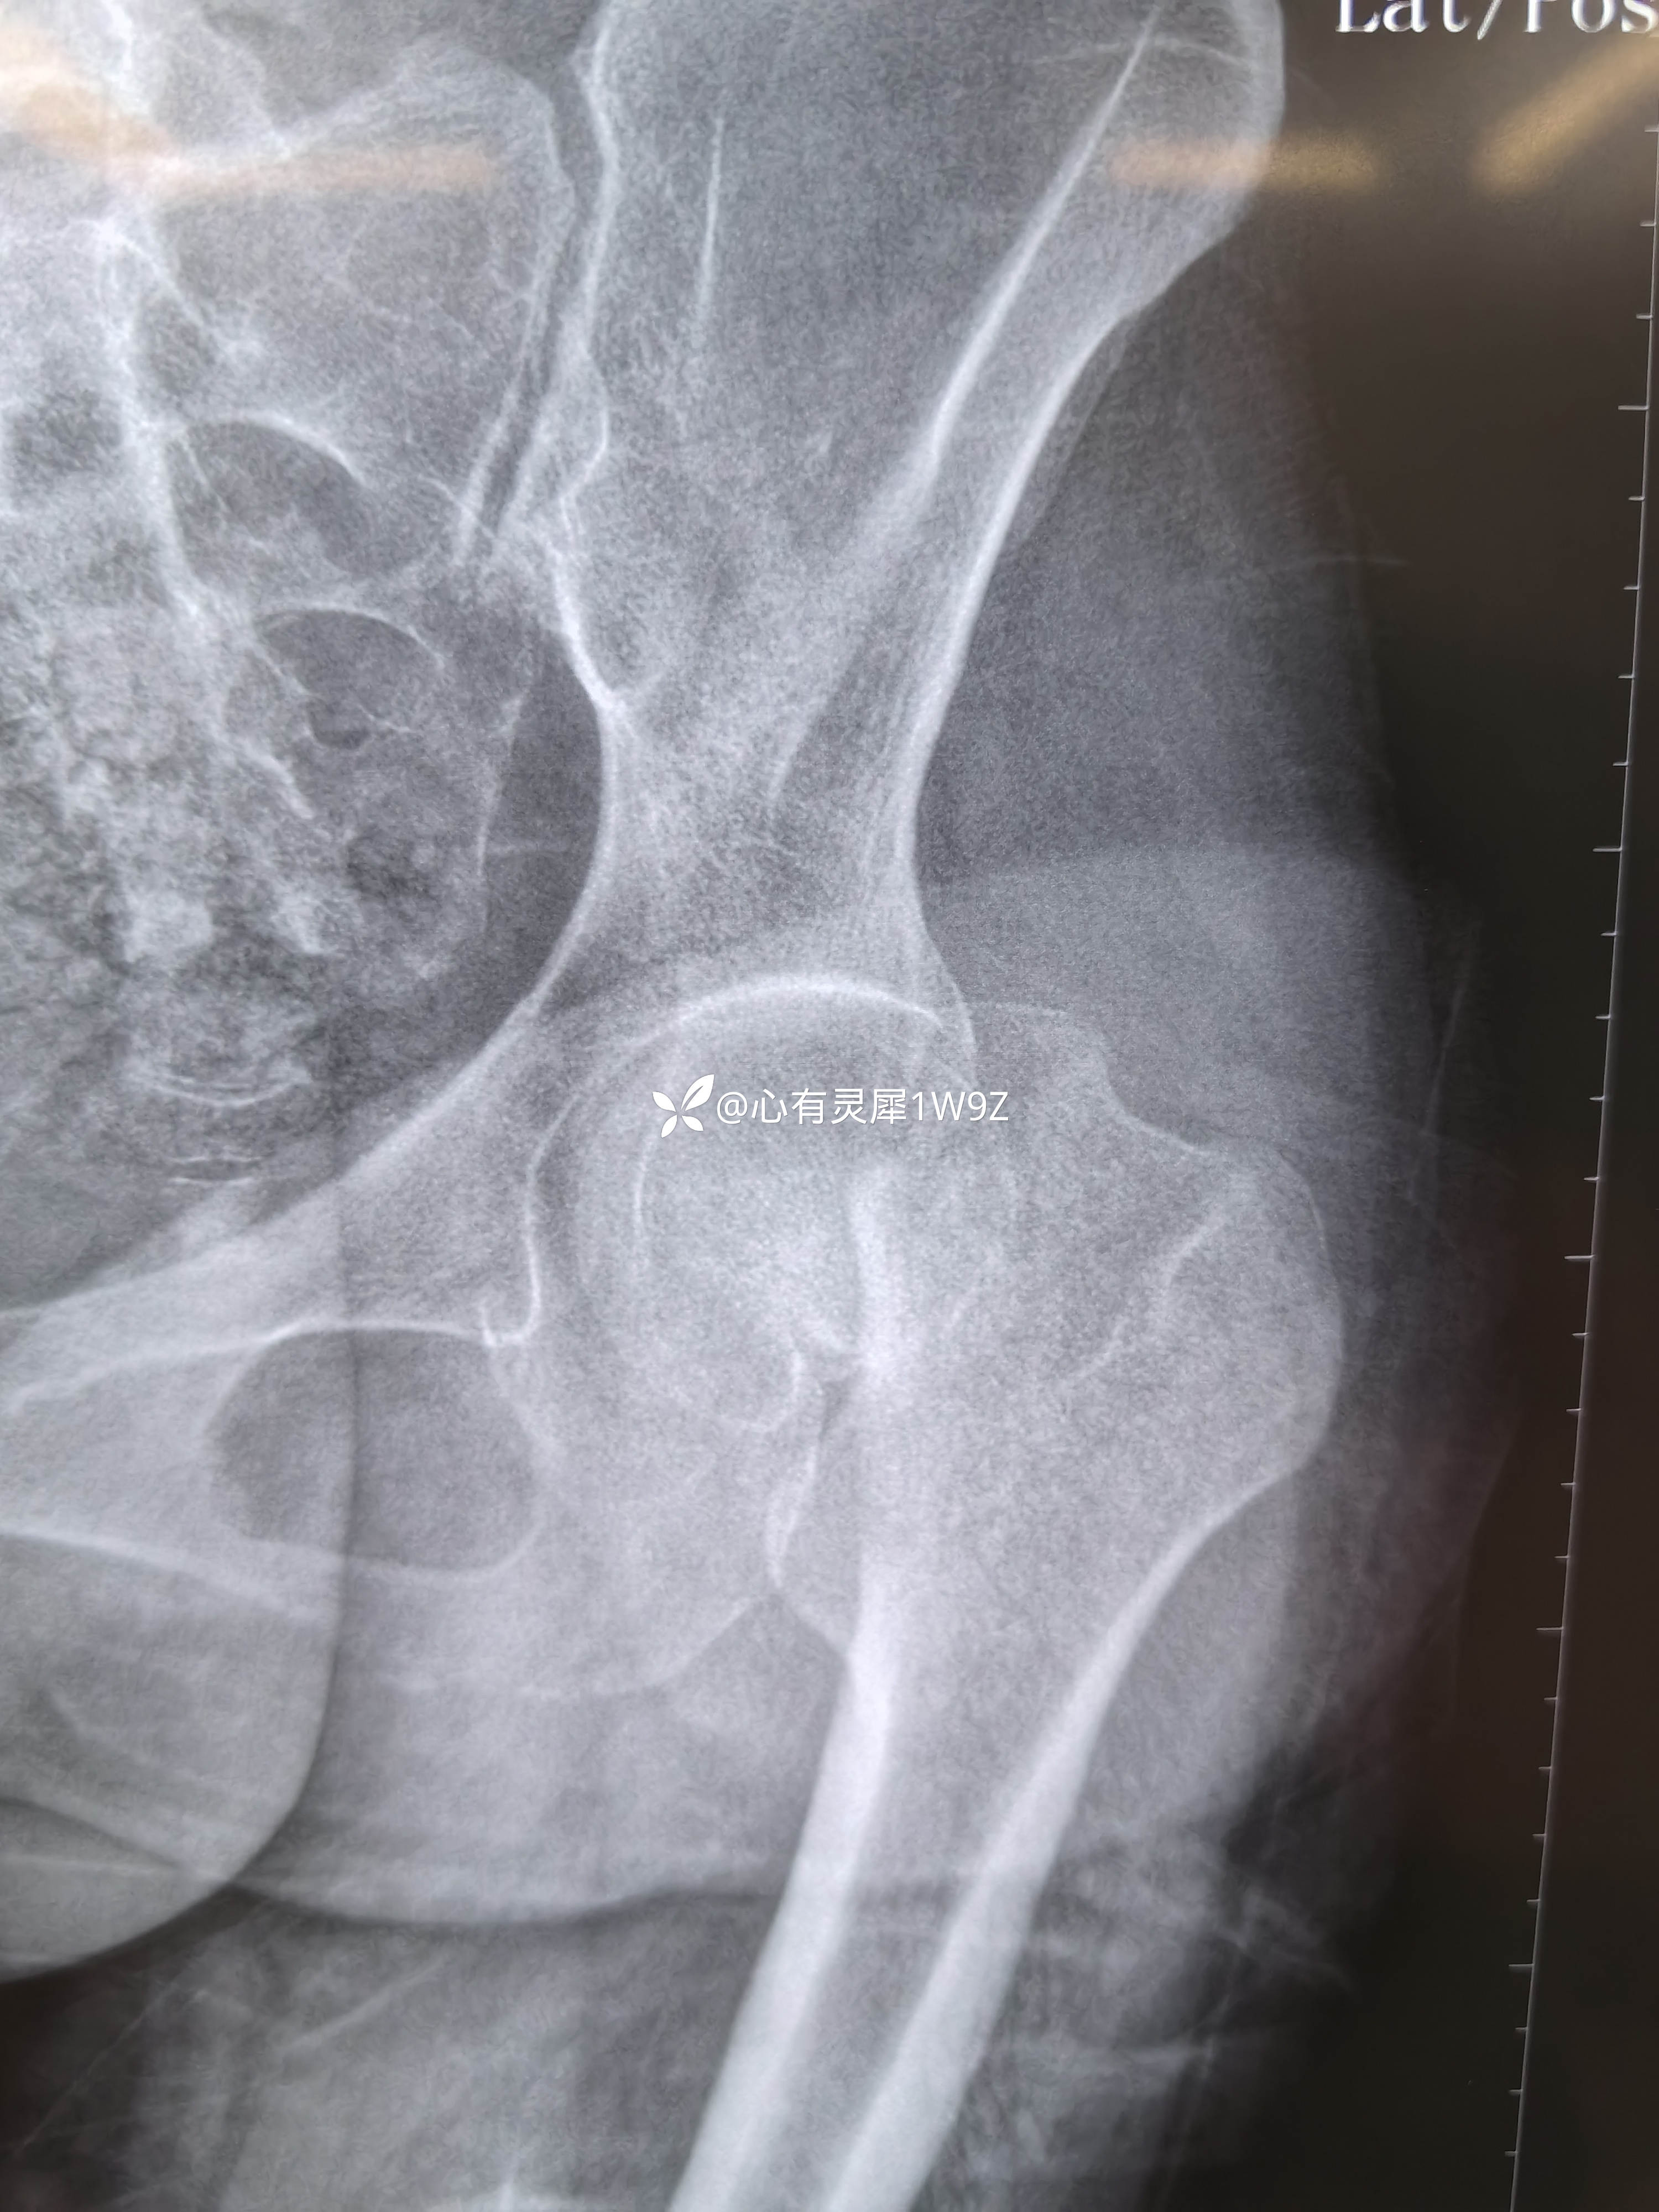

诊断:左侧股骨颈骨折(头下型)garden IV型

1,关于闭合复位的一些经验,该患者牵引床,先外旋外展牵引解锁后透视正位,根据情况再调整牵引内旋透视复位侧位。最后再内旋内收定位画线。

2,关于贴壁,平行,长度,角度。自己感觉这次平行和长度都比较满意,贴壁还可以,角度不是很完美,感觉可以接受,就没有再调整。